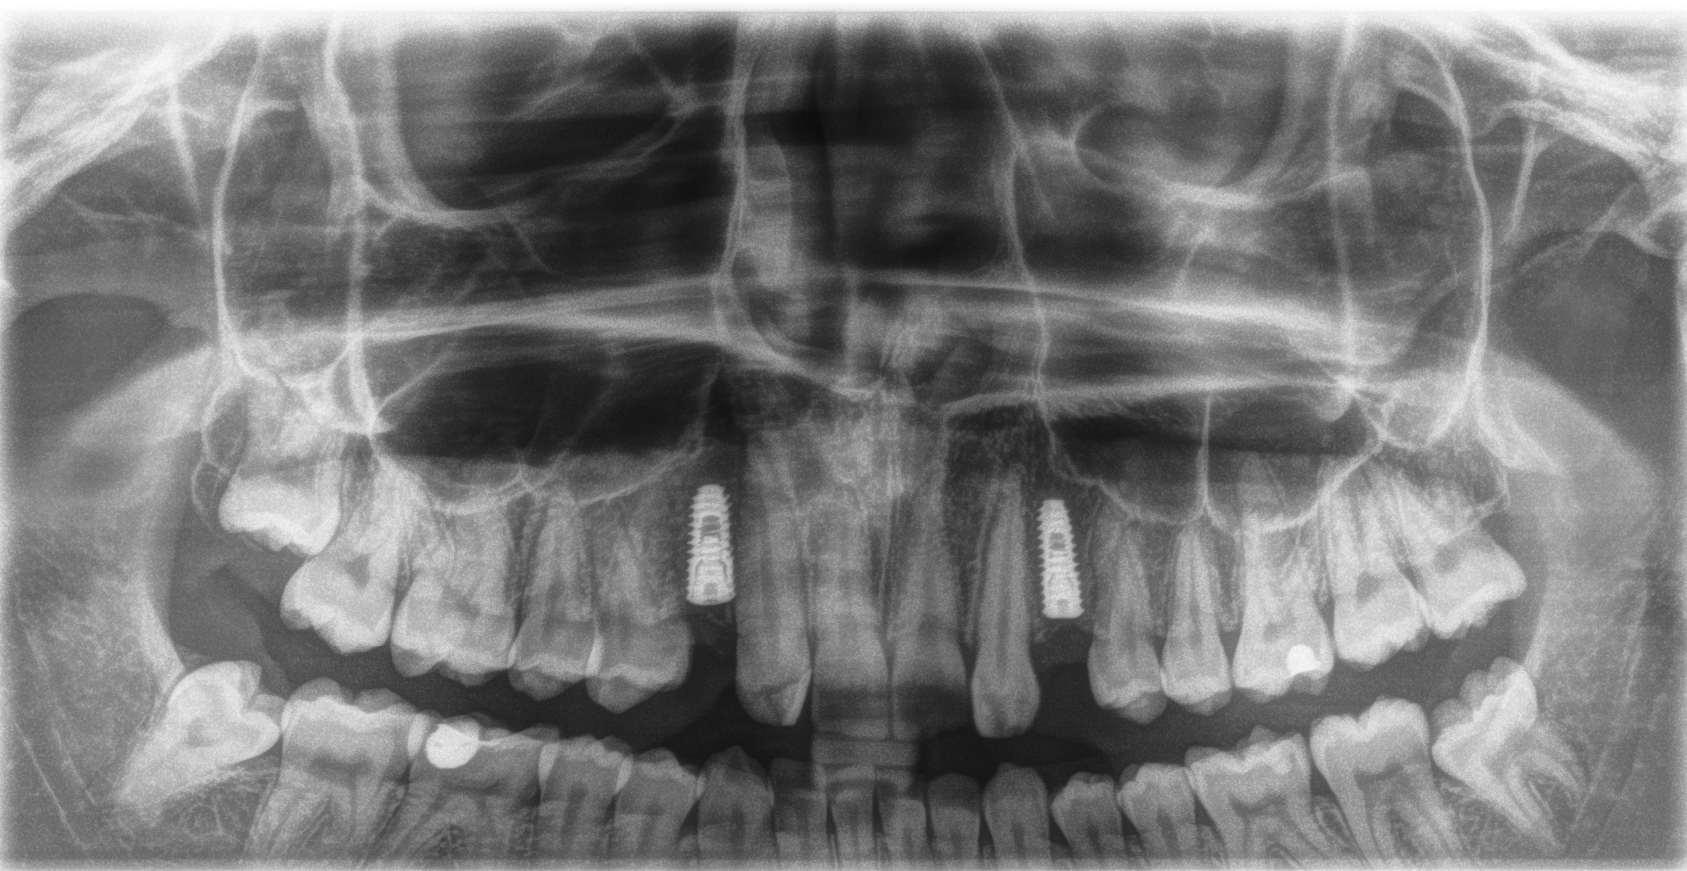

Radiologinen näkymä lopputilanteesta. Implanttikruunut paikoillaan.

Sama tilanne toiselta puolelta